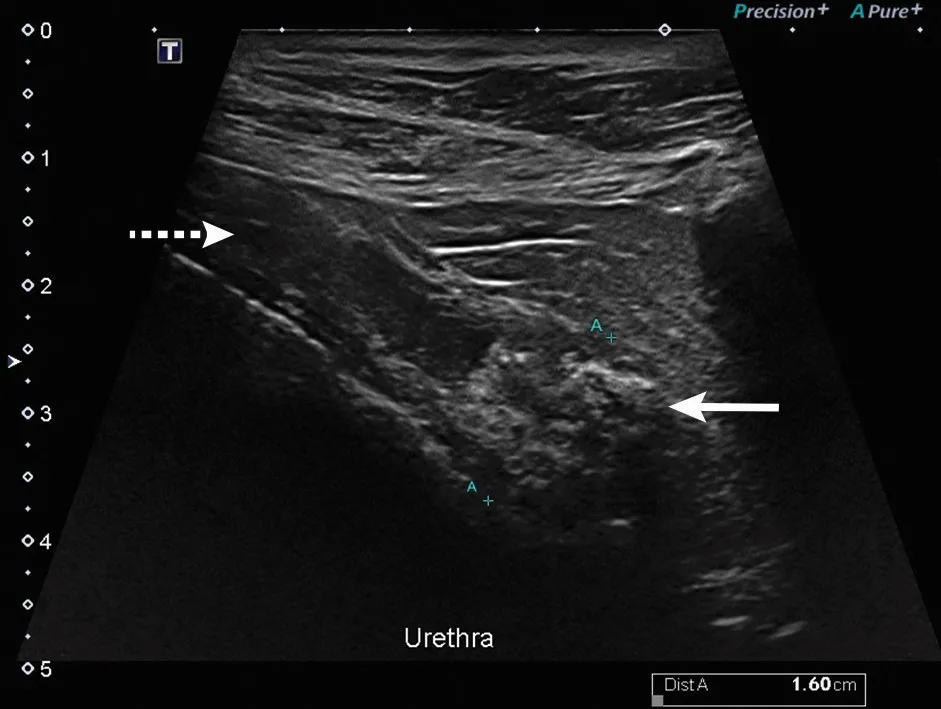

Transitional cell carcinoma is the most common neoplasia in the urinary system of dogs.10 These tumors are commonly found at the trigone of the bladder and/or urethra, in which a thickening or mass may be palpable at the pelvic urethra during rectal examination.11 Further diagnostics (eg, abdominal ultrasonography) may be warranted if clinical signs and examination abnormalities are found (Figure 2). Imaging results suggestive of a mass indicate the need for further evaluation with molecular urine testing.12,13

Microscopic image of cells from an anal sac tumor.

FIGURE 2

Ultrasound of the urethra (dashed arrow) of a dog with transitional cell carcinoma. A mixed echogenic mass within the lumen of the urethra can be seen (solid arrow). Image courtesy of Merrilee Holland, DVM, DACVR